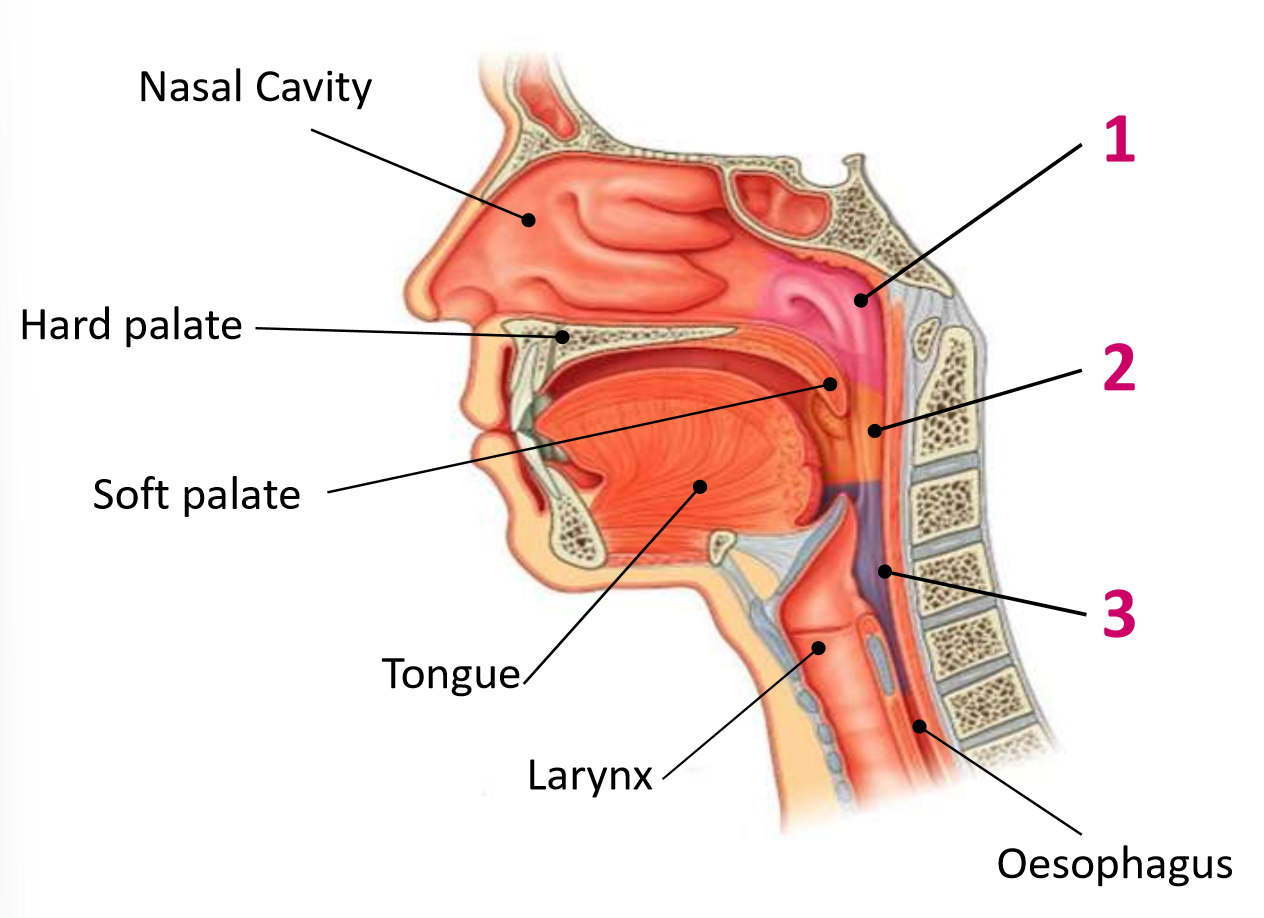

Which area of the head and neck do 1, 2, and 3 make?

pharynx

What region is 1?

nasopharynx

What region is 2?

oropharynx

What region is 3?

laryngopharynx